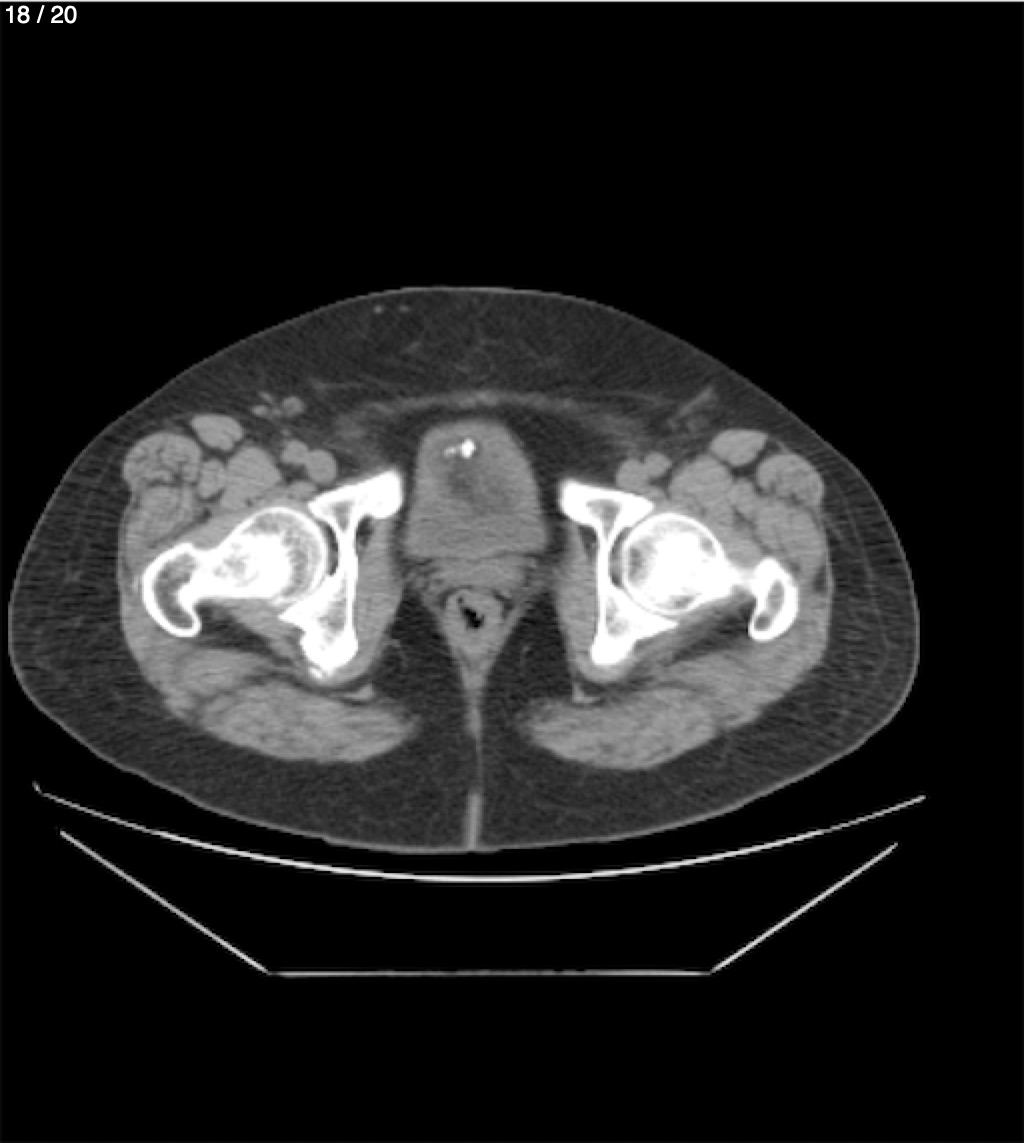

Maria Enrique Giron Dominguez63A - T.C Abdomen Simple